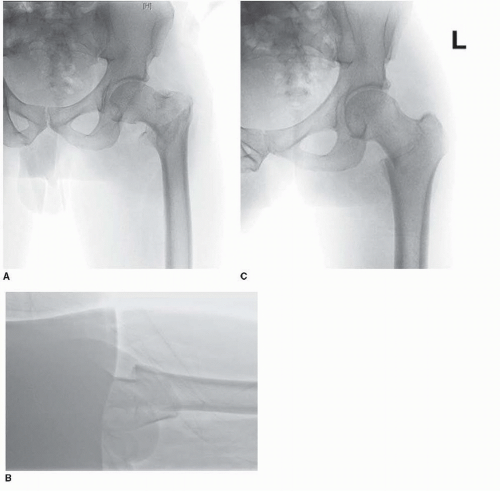

Diseases of the digestive system. The icd code s720 is used to code hip fracture a hip fracture is a serious femoral fracture that occurs in the proximal end of the femur (the long bone running through the thigh), near the hip. Search about 41 items found relating to hip fracture

821 fracture of other and unspecified parts of femur; The icd code s720 is used to code hip fracture a hip fracture is a serious femoral fracture that occurs in the proximal end of the femur (the long bone running through the thigh), near the hip.